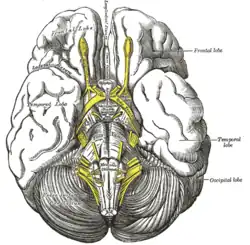

Tuber cinereum hamartoma is a benign tumor in which a disorganized collection of neurons and glia accumulate at the tuber cinereum of the hypothalamus on the floor of the third ventricle. It is a congenital malformation, included on the spectrum of gray matter heterotopias. Formation occurs during embryogenesis, typically between days 33 and 41 of gestation. Size of the tumor varies from one to three centimeters in diameter, with the mean being closer to the low end of this range. It is estimated to occur at a frequency of one in one million individuals.[1]